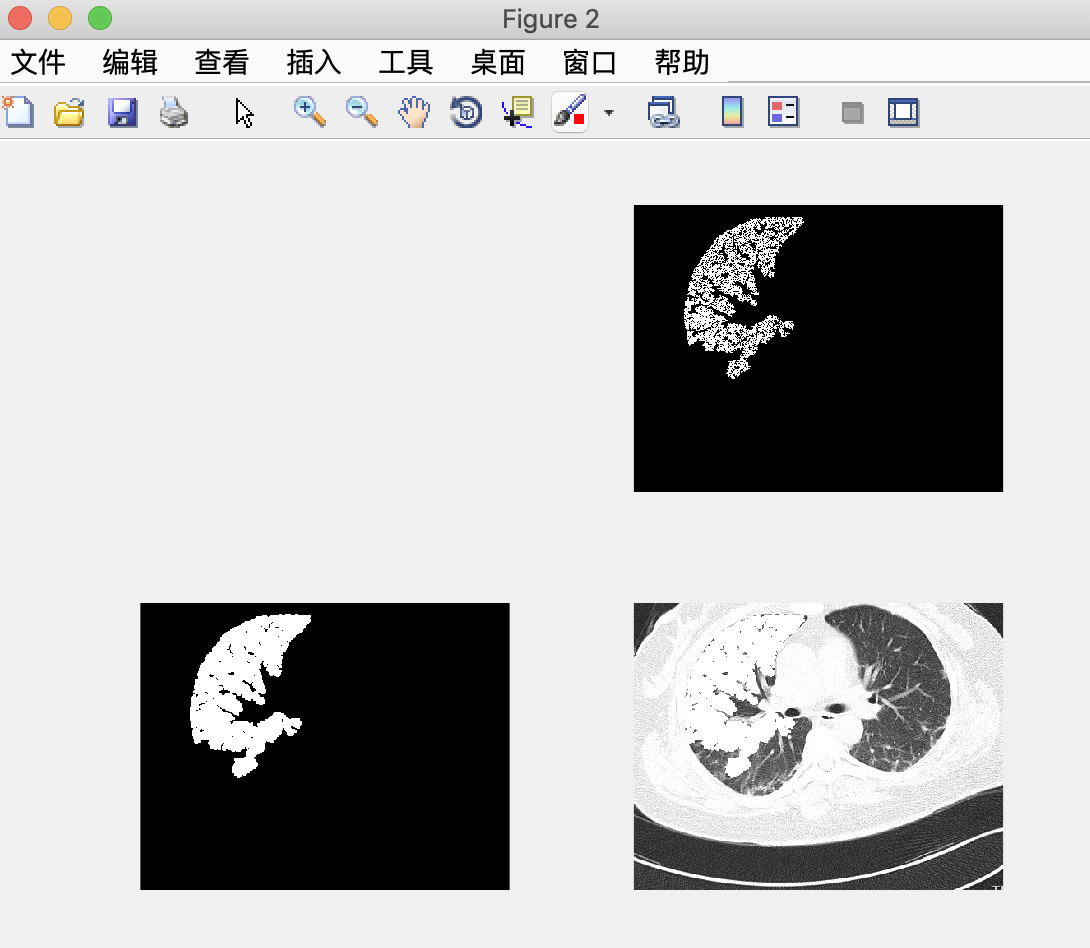

结果:

以下为原图,先转化为灰度图,再转换为二值图。

鼠标先在二值图左肺选取一个种子点,按‘b‘进行分割;然后在二值图右肺选取一个种子点,按‘b‘进行分割,之后做或运算,将两个分割结果合并;最后与灰度图做与运算得到最终分割结果。

结果:

由于只选取了一个点,效果不是特别好。